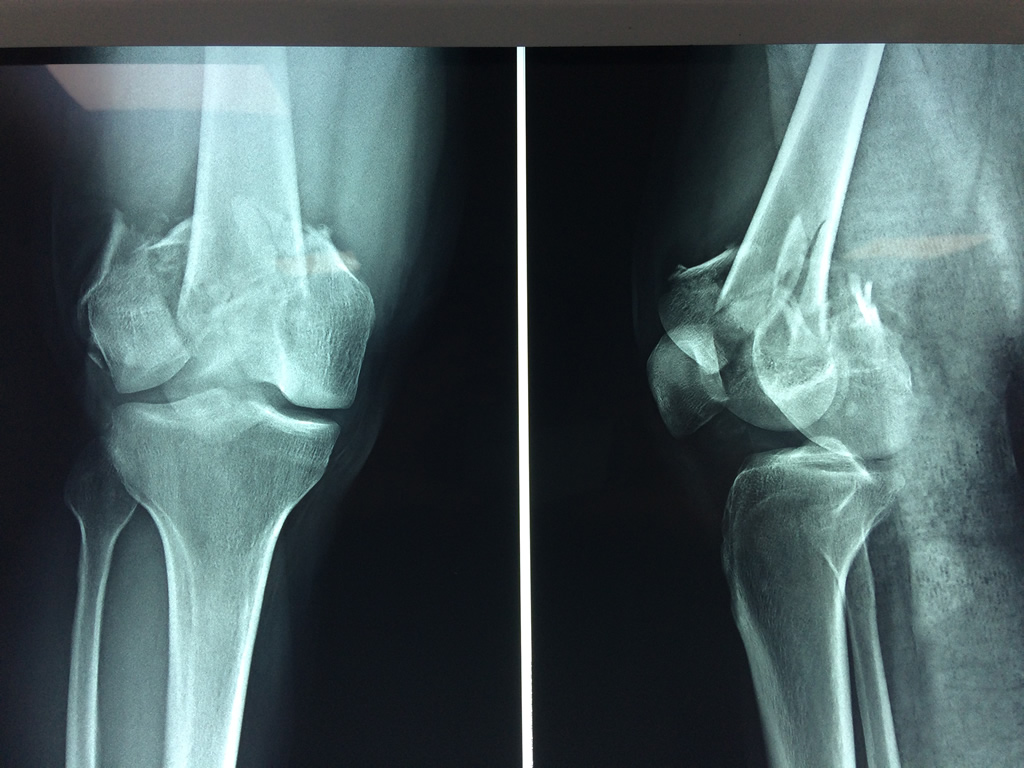

Cirugías de Hombros - Fémur

El fémur es el hueso del muslo, el segundo segmento del miembro inferior. Es el hueso más largo, fuerte y voluminoso del cuerpo humano.